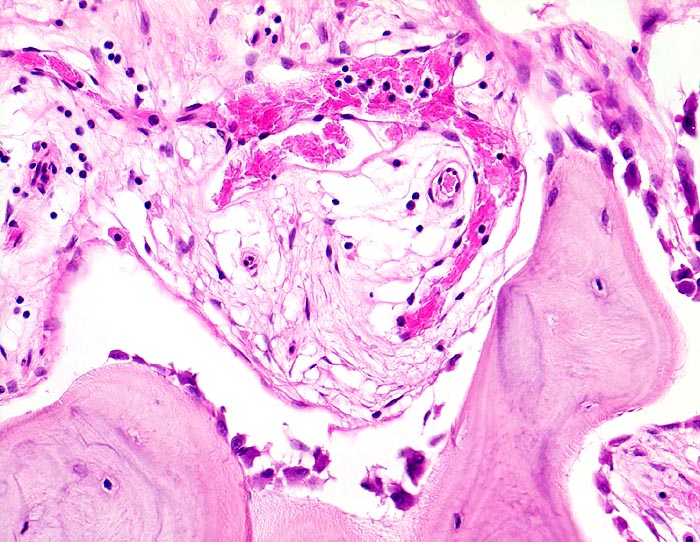

An den betroffenen Stellen ist sowohl der Knochenabbau als auch der Knochenanbau gesteigert. Die Osteoklasten sind auffallend gross und enthalten sehr viele Kerne (> 3518). Die aktivierten Osteoblasten produzieren verdickte und grob geflochtene Spongiosabälkchen. Der neugebildete Knochen ist strukturell und morphologisch abnorm und schlecht mineralisiert. Der Knochen wird dadurch weich und anfällig auf Frakturen oder Deformation unter Belastung (nach vorne gebogene Säbelscheidentibia). Das Knochenmark wird ersetzt durch fibrovaskuläres lockeres Stroma, welches an Granulationsgewebe erinnert. Mikroskopisch werden eine osteolytische Initialphase, eine Umbauphase mit verstärkter Knochenneubildung und eine sklerosierende Stabilisationsphase mit strukturellem Umbau und Spongiosierung der Kortikalis (verbreiterte spongiosaartige Kortikalis) unterschieden.

• Die Spongiosabälkchen sind auffallend verdickt, vermehrt und unregelmässig geformt.

• Prominente Zementlinien sind mosaikartig angeordnet.

• Riesenosteoklasten mit über 20 Kernen sind an der Knochenoberfläche erkennbar.

• Vermehrte kubische aktive Osteoblasten bauen Knochen an.

• Lockere Markfibrose.